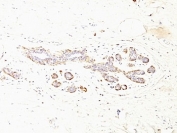

IHC: Formalin-fixed, paraffin-embedded human breast carcinoma stained with SMMHC antibody (MYH11/923 + SMMS-1).